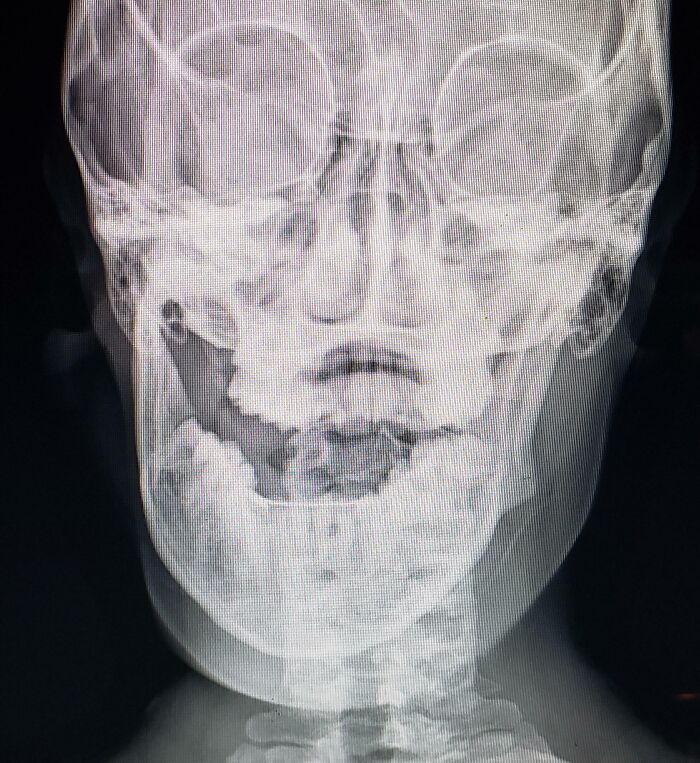

A Fear Of Eating Too Hard

I dislocated my jaw... While eating cereal.

Load More Replies...It happens for some people with hyperlaxity (not sure that's the correct translation)